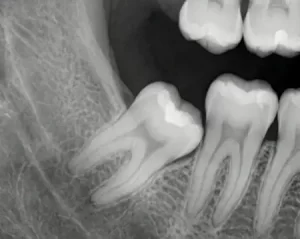

Процедуре обязательно предшествует 3D-снимок челюстей (КЛКТ), на котором стоматолог может детально рассмотреть анатомические особенности «восьмерки» и спланировать способ удаления. Если речь идет о ретинированном зубе, без снимка никакие действия не предпринимаются.

Они могут располагаться как на верхней, так и на нижней челюсти. Ретинированные зубы мудрости частично или полностью погружены в кость и прикрыты десной. Дистопированные — имеют аномальное положение, могут быть смещены в сторону щеки или языка, повернуты вокруг своей оси или наклонены.